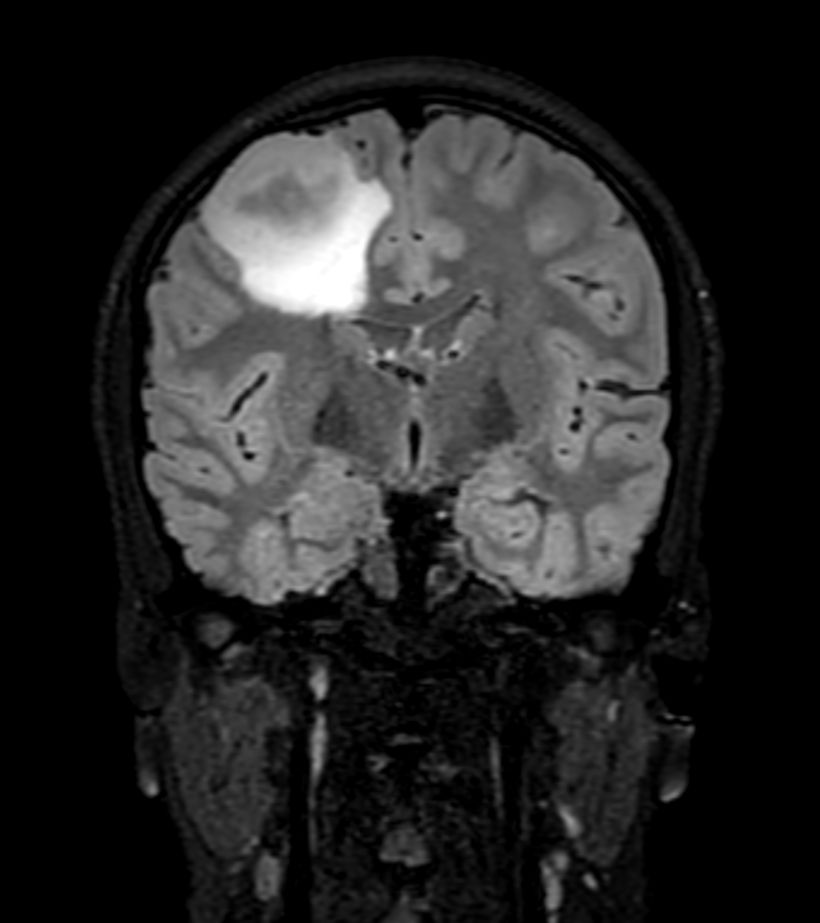

3D T2w FLAIR - Coronal Reformat Compressed SENSE

3D T2w FLAIR - Axial Reformat Compressed SENSE